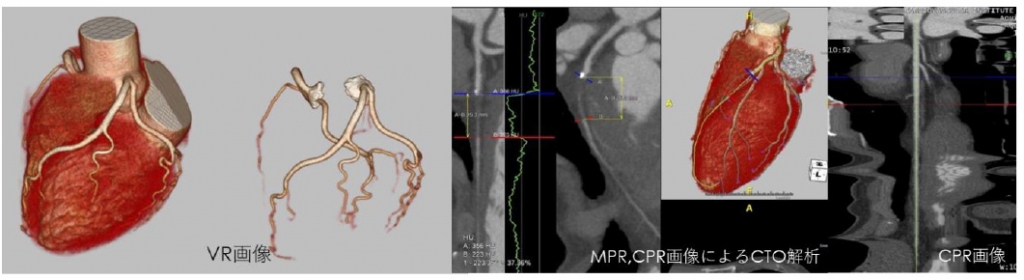

冠動脈CT

単純・造影像を撮影し冠動脈石灰化評価、狭窄評価、バイパス術やステント留置後の評価を行います。

心電図同期を用い標的位相のみを1スキャンで撮影することで、被ばくは従来64列CTの1/4程度に低減され、胸部単純CTと同程度の少ない被ばくで検査を受けて頂けます1)

血管拡張のためニトロ舌下スプレーを使用。撮影時の理想心拍数は65以下となりますので、必要によりβ遮断薬2)を使用し最適心拍数に近づけます。

15分程度の検査で造影剤量は体重Kg×0.7ml程度となります1)

1)検査内容や撮影条件により多少の変動があります

2)コアベータ静注用12.5mg

STENT症例

従来の金属アーチファクトを低減しSTENT内をきれいに描出します。

バイパス術後症例

冠動脈のほかにLITA,RITA,SVGなど冠動脈バイパスの術後評価が可能です。

冠動脈石灰化評価(カルシウムスコア)

冠動脈の石灰化スコアを算出することで動脈硬化の度合いを調べます。このスコアは将来の冠動脈疾患の危険度を予測するデータの一つになるとされています。非造影検査ですので造影剤を用いることなく評価できます。

冠動脈CT検査と同時に検査し、石灰化病変がある場合のみ評価レポートを出力します。